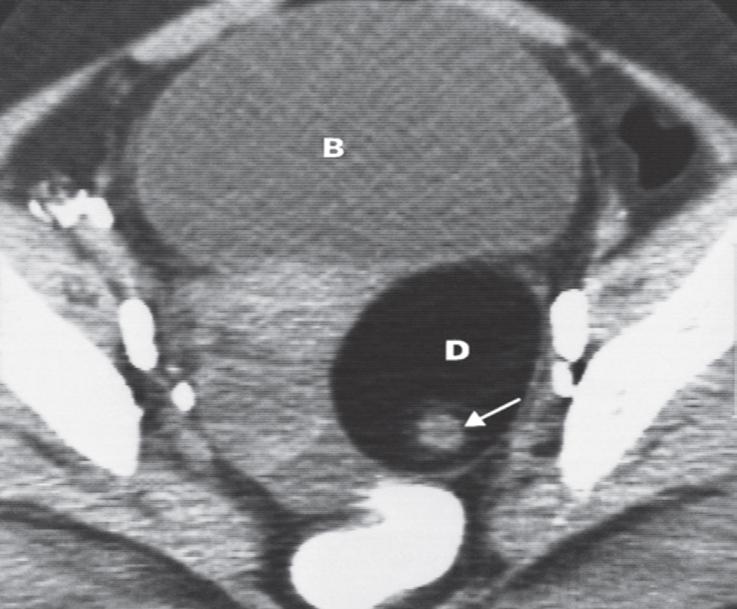

Dermoid cyst. CT scan

showing the oval-shaped fat density of a dermoid cyst (D) containing calcified material (arrow). B, bladder.